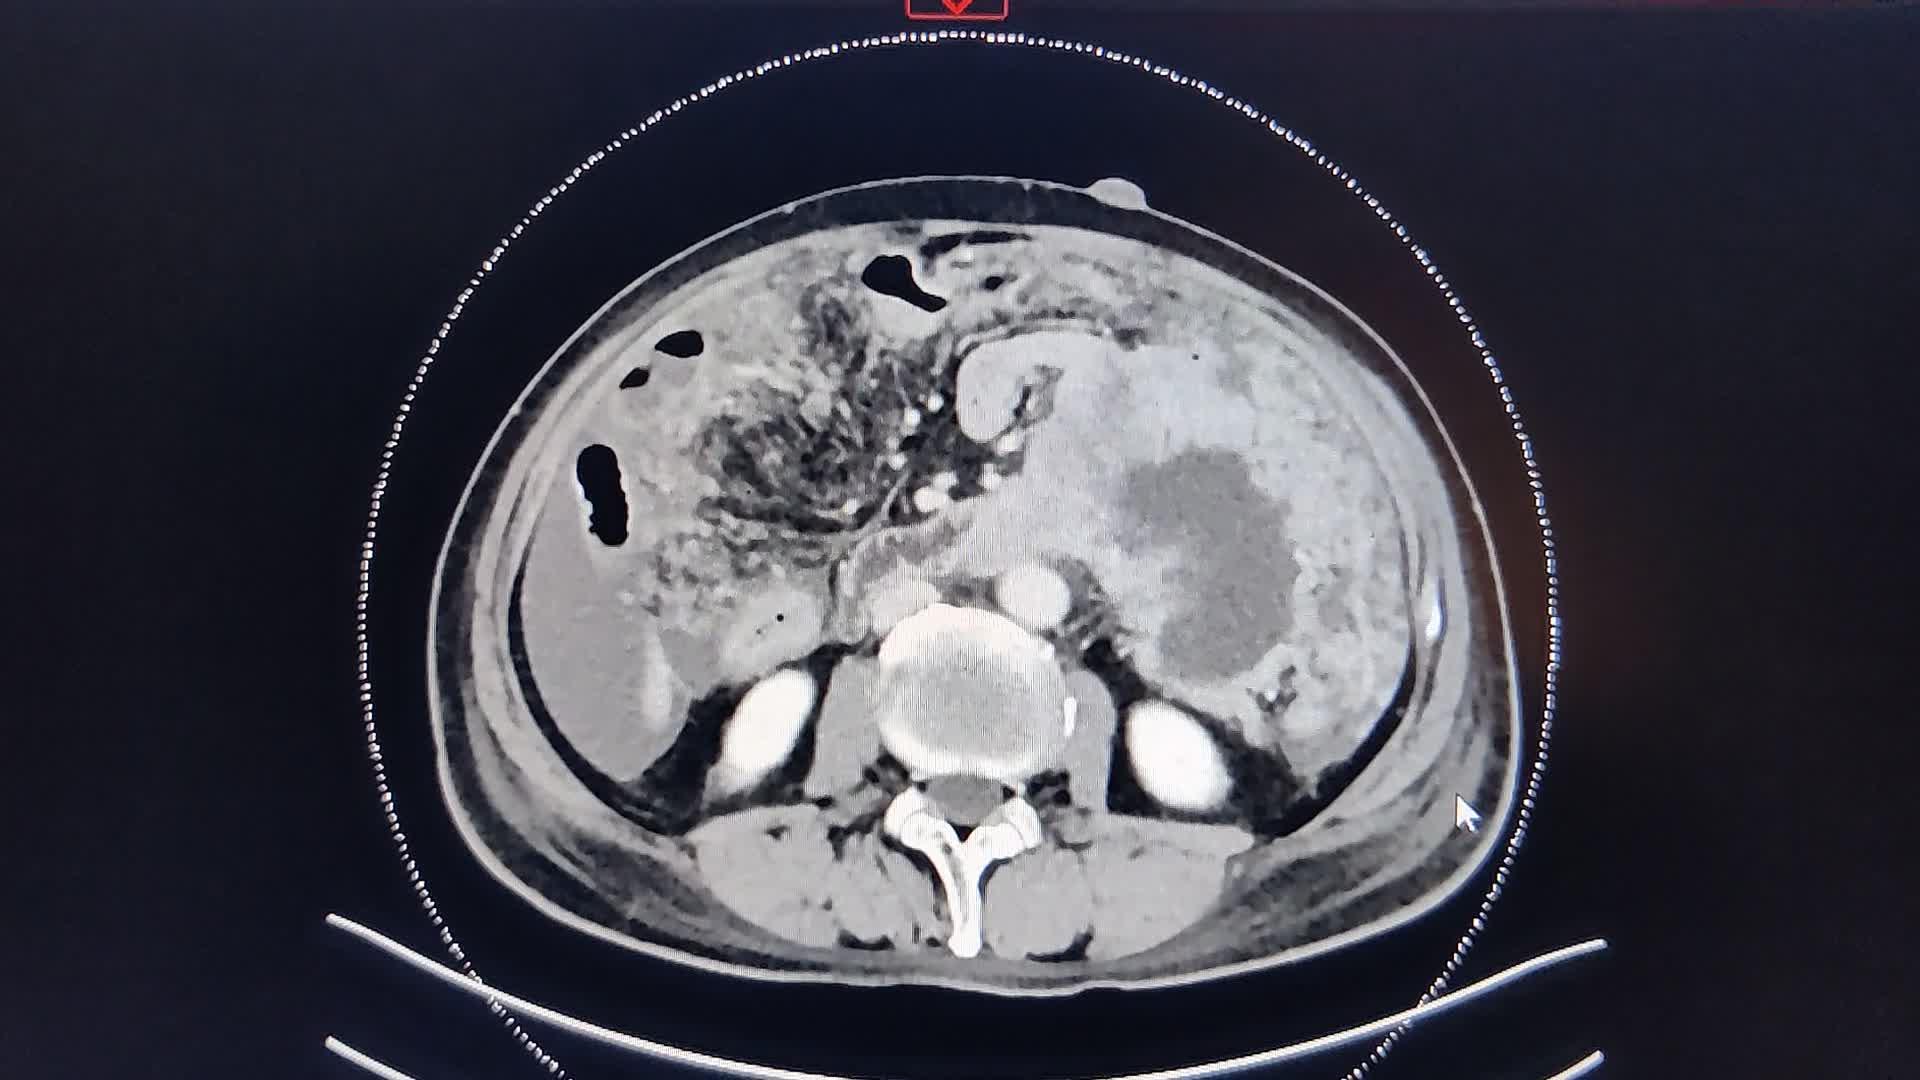

晚期腹腔间质瘤(胃肠间质瘤),减瘤成功解除梗阻,附ct图像,难度不低!

图片尺寸1920x1080